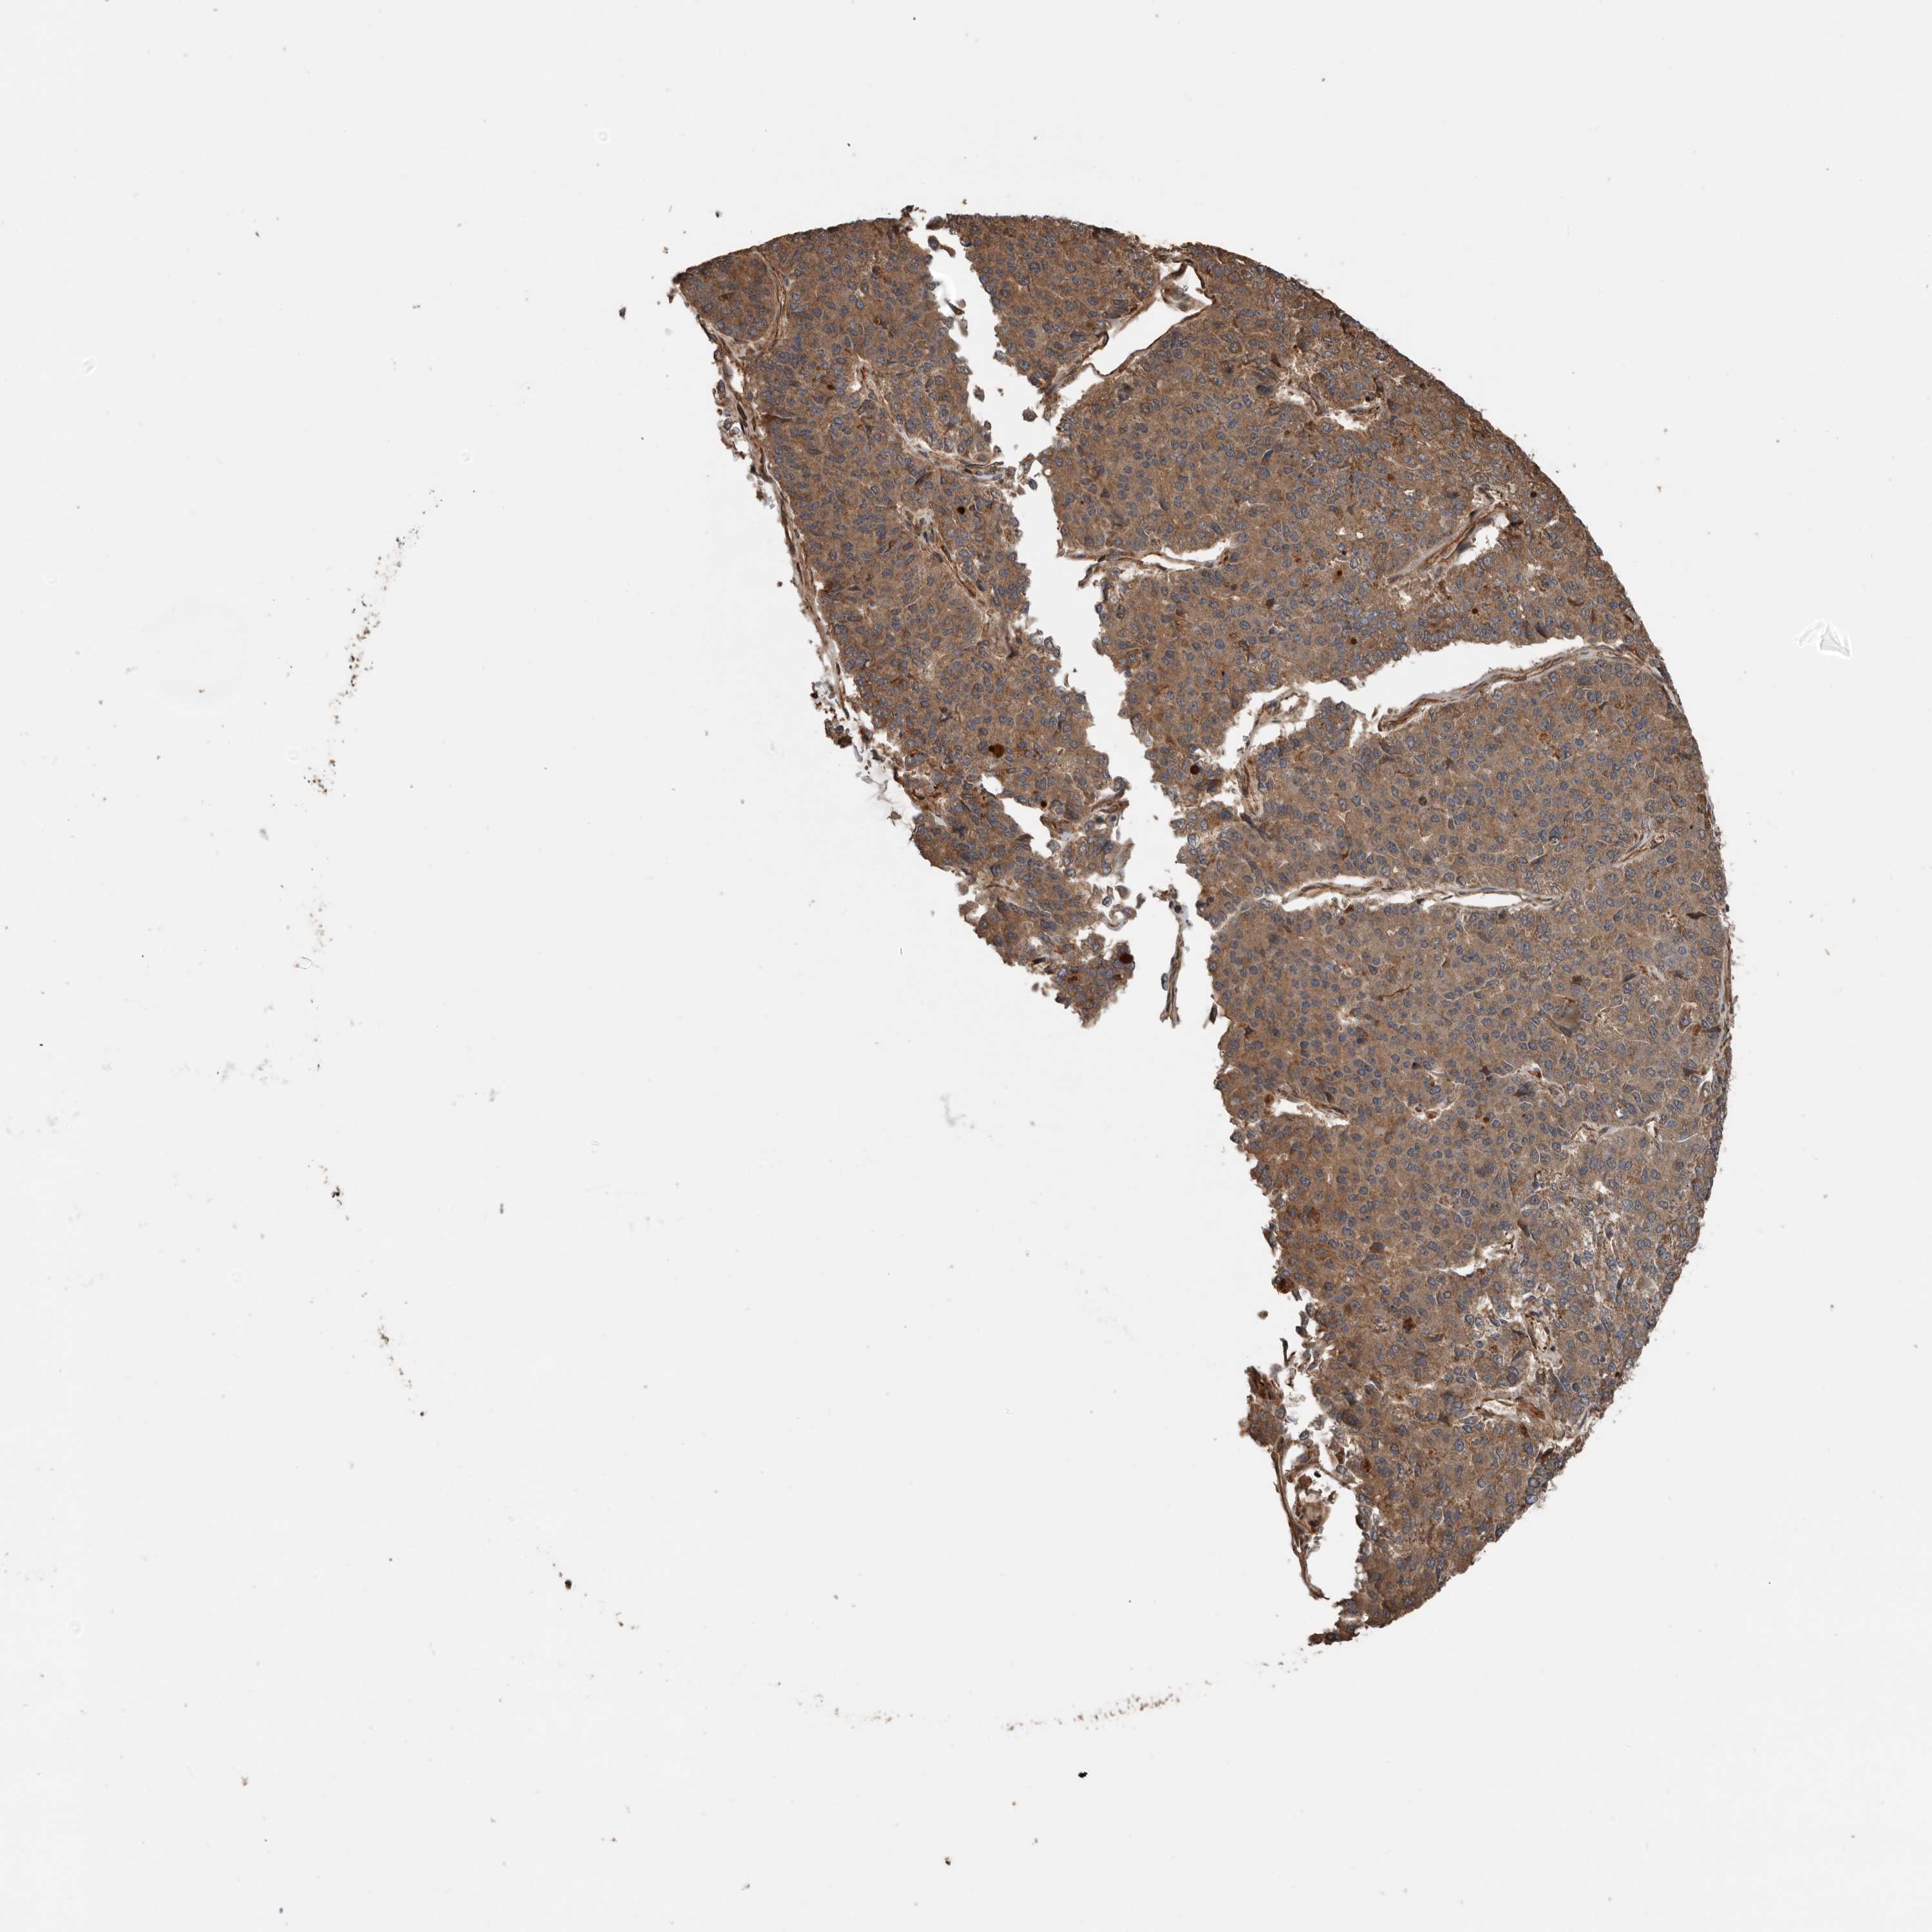

PANCREATIC CANCER - Protein expressioni

A mouse-over function shows sample information and annotation data. Click on an image to view it in a full screen mode. Samples can be filtered based on level of antibody staining by selecting one or several of the following categories: high, medium, low and not detected. The assay and annotation is described here.

Note that samples used for immunohistochemistry by the Human Protein Atlas do not correspond to samples in the TCGA dataset.

Antibody stainingi

Antibody staining in the annotated cell types in the current human tissue is reported as not detected, low, medium, or high, based on conventional immunohistochemistry profiling in selected tissues. This score is based on the combination of the staining intensity and fraction of stained cells.

Each image is clickable and will lead to virtual microscopy that enables deeper exploration of all samples and also displays staining intensity scores, fraction scores and subcellular localization as well as patient and tissue information for each sample.

Antibody HPA028400

Antibody HPA028439

Staining

High

Medium

Low

Not detected

Intensity

Strong

Moderate

Weak

Negative

Quantity

>75%

75%-25%

<25%

None

Location

Nuclear

Cytoplasmic/membranous

Cytoplasmic/membranous,nuclear

Adenocarcinoma, NOS